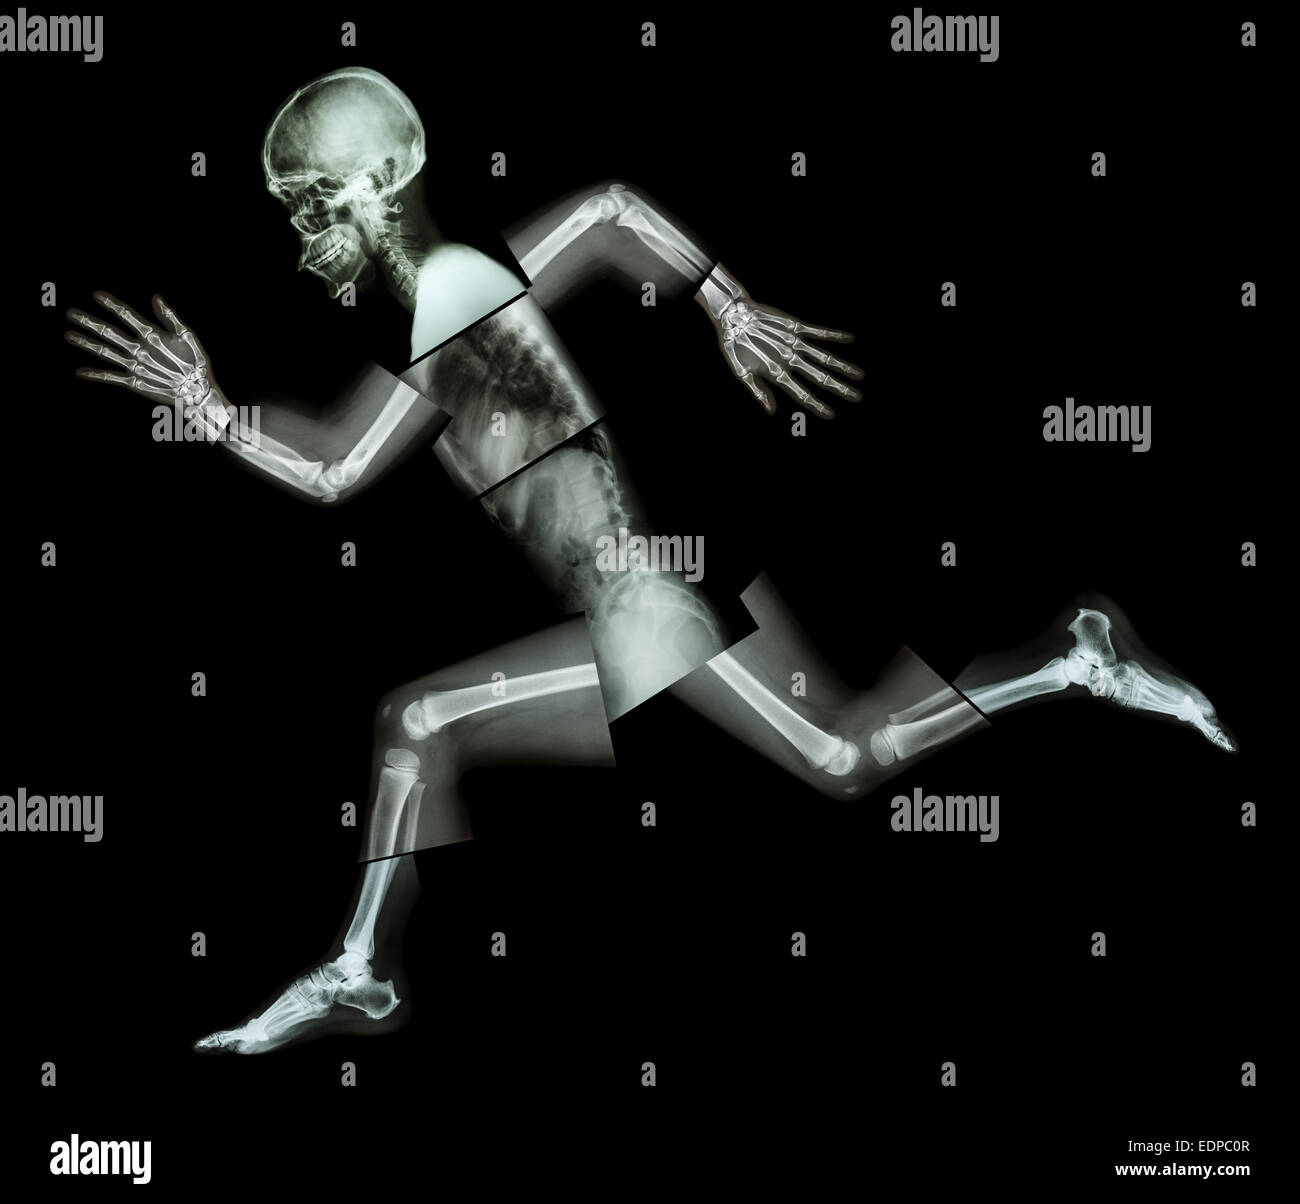

Marathon (les droits de l'os est en marche) ,(corps entier x-ray : tête, cou, bras, épaule, coude, avant-bras, main, doigt ,,commune thorax ,ab Banque D'Imageshttps://www.alamyimages.fr/image-license-details/?v=1https://www.alamyimages.fr/photo-image-marathon-les-droits-de-l-os-est-en-marche-corps-entier-x-ray-tete-cou-bras-epaule-coude-avant-bras-main-doigt-commune-thorax-ab-77324375.html

Marathon (les droits de l'os est en marche) ,(corps entier x-ray : tête, cou, bras, épaule, coude, avant-bras, main, doigt ,,commune thorax ,ab Banque D'Imageshttps://www.alamyimages.fr/image-license-details/?v=1https://www.alamyimages.fr/photo-image-marathon-les-droits-de-l-os-est-en-marche-corps-entier-x-ray-tete-cou-bras-epaule-coude-avant-bras-main-doigt-commune-thorax-ab-77324375.htmlRFEDPC0R–Marathon (les droits de l'os est en marche) ,(corps entier x-ray : tête, cou, bras, épaule, coude, avant-bras, main, doigt ,,commune thorax ,ab

Marathon (les droits de l'os est en marche) ,(corps entier x-ray : tête, cou, bras, épaule, coude, avant-bras, main, doigt ,,commune thorax ,ab Banque D'Imageshttps://www.alamyimages.fr/image-license-details/?v=1https://www.alamyimages.fr/photo-image-marathon-les-droits-de-l-os-est-en-marche-corps-entier-x-ray-tete-cou-bras-epaule-coude-avant-bras-main-doigt-commune-thorax-ab-77324374.html

Marathon (les droits de l'os est en marche) ,(corps entier x-ray : tête, cou, bras, épaule, coude, avant-bras, main, doigt ,,commune thorax ,ab Banque D'Imageshttps://www.alamyimages.fr/image-license-details/?v=1https://www.alamyimages.fr/photo-image-marathon-les-droits-de-l-os-est-en-marche-corps-entier-x-ray-tete-cou-bras-epaule-coude-avant-bras-main-doigt-commune-thorax-ab-77324374.htmlRFEDPC0P–Marathon (les droits de l'os est en marche) ,(corps entier x-ray : tête, cou, bras, épaule, coude, avant-bras, main, doigt ,,commune thorax ,ab

Marathon (les droits de l'os est en marche) ,(corps entier x-ray : tête, cou, bras, épaule, coude, avant-bras, main, doigt ,,commune thorax ,ab Banque D'Imageshttps://www.alamyimages.fr/image-license-details/?v=1https://www.alamyimages.fr/photo-image-marathon-les-droits-de-l-os-est-en-marche-corps-entier-x-ray-tete-cou-bras-epaule-coude-avant-bras-main-doigt-commune-thorax-ab-77323572.html

Marathon (les droits de l'os est en marche) ,(corps entier x-ray : tête, cou, bras, épaule, coude, avant-bras, main, doigt ,,commune thorax ,ab Banque D'Imageshttps://www.alamyimages.fr/image-license-details/?v=1https://www.alamyimages.fr/photo-image-marathon-les-droits-de-l-os-est-en-marche-corps-entier-x-ray-tete-cou-bras-epaule-coude-avant-bras-main-doigt-commune-thorax-ab-77323572.htmlRFEDPB04–Marathon (les droits de l'os est en marche) ,(corps entier x-ray : tête, cou, bras, épaule, coude, avant-bras, main, doigt ,,commune thorax ,ab

Marathon (les droits de l'os est en marche) ,(corps entier x-ray : tête, cou, bras, épaule, coude, avant-bras, main, doigt ,,commune thorax ,ab Banque D'Imageshttps://www.alamyimages.fr/image-license-details/?v=1https://www.alamyimages.fr/photo-image-marathon-les-droits-de-l-os-est-en-marche-corps-entier-x-ray-tete-cou-bras-epaule-coude-avant-bras-main-doigt-commune-thorax-ab-77324380.html

Marathon (les droits de l'os est en marche) ,(corps entier x-ray : tête, cou, bras, épaule, coude, avant-bras, main, doigt ,,commune thorax ,ab Banque D'Imageshttps://www.alamyimages.fr/image-license-details/?v=1https://www.alamyimages.fr/photo-image-marathon-les-droits-de-l-os-est-en-marche-corps-entier-x-ray-tete-cou-bras-epaule-coude-avant-bras-main-doigt-commune-thorax-ab-77324380.htmlRFEDPC10–Marathon (les droits de l'os est en marche) ,(corps entier x-ray : tête, cou, bras, épaule, coude, avant-bras, main, doigt ,,commune thorax ,ab